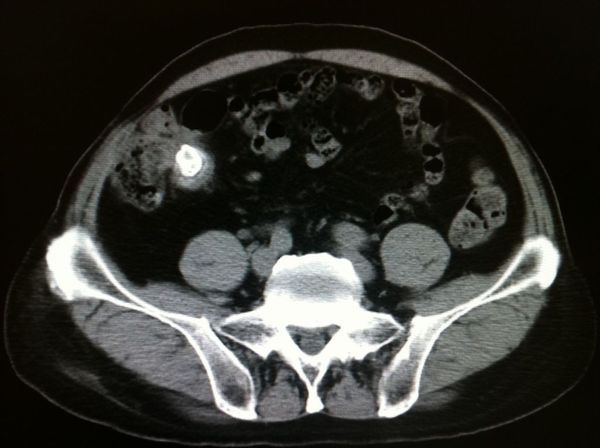

阑尾炎并粪石形成,阑尾周围可见渗出

图片尺寸1200x1200